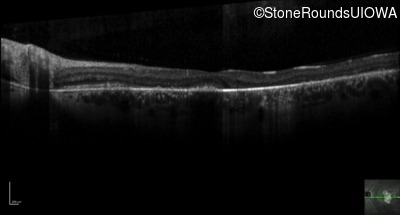

Optical Coherence Tomography - Right - 20/40

Exemplar / OCT Stack

OCT Stack